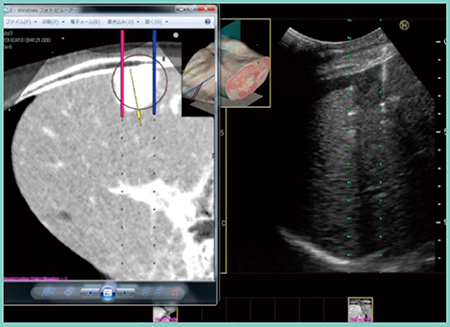

シミュレーションは前述の方法にて人工腹水を併用して治療前日に行い,当日はリファレンス画像を参照しながら,まずは北半球の穿刺を行った(図3,4)。その後,画面表示をReal-time Biplaneに切り替え,凝固域の広がりを見ながら穿刺位置を微調整しつつ焼灼した。続いて南半球も同様に穿刺(図5),焼灼を行い,最後に凝固域の分裂がないことを確認した。治療後のCTでは,凝固域がほぼ球形を成し,コロナ濃染も含めて十分なマージンを形成できていることが確認できた。

図5 実証試技における南半球の穿刺